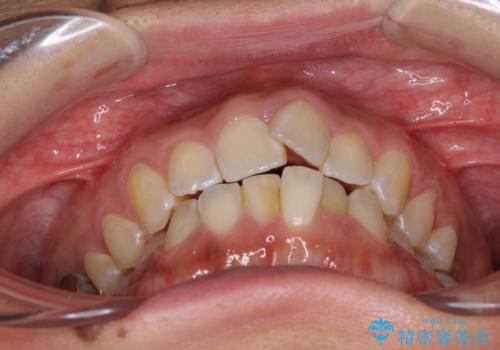

インビザラインによる狭窄歯列の拡大矯正

- 前歯のデコボコを治したいとのことで来院された患者様です。

上下顎ともに歯列全体の後方移動と側方拡大、IPR(歯と歯の間を削る)によってデコボコが解消するように設計し、インビザラインにより治療を行うこととしました。

後方移動に際し、上下の親知らずは4本とも抜歯することとしました。